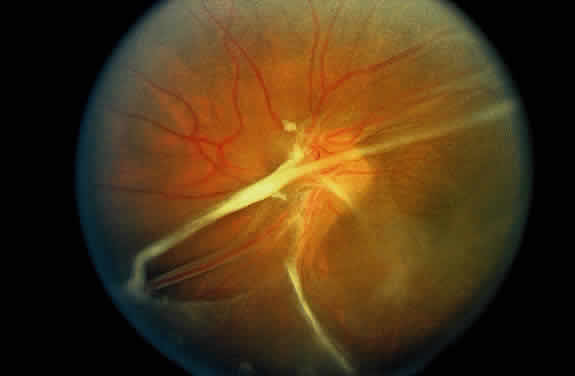

As a result of the retinal nonperfusion, new vessels can form either on the disc (neovascularization of the disc) or, more commonly, neovascularization can occur elsewhere in the retina (Fig. 5). These abnormal blood vessels can hemorrhage and are the major cause of visual loss in this disease. The neovascularization in the peripheral retina usually occurs at the junction of perfused and nonperfused retina, similar to the appearance of neovascularization in the peripheral retina in diabetic retinopathy and the other peripheral proliferative retinopathies. Neovascularization can be associated with extensive fibrovascular proliferation and fibrosis (Fig. 6). The anteroposterior and tangential traction resulting from the fibrovascular proliferation places these eyes at risk for development of retinal detachment. Neovascularization of the iris also has been described.